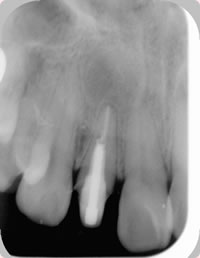

術後数カ月~1年程度経過をみてレントゲンを撮影し、骨が再生されていれば治癒したと判定できます(図3)。

図3 1年後のレントゲン写真.骨が再生され治癒している